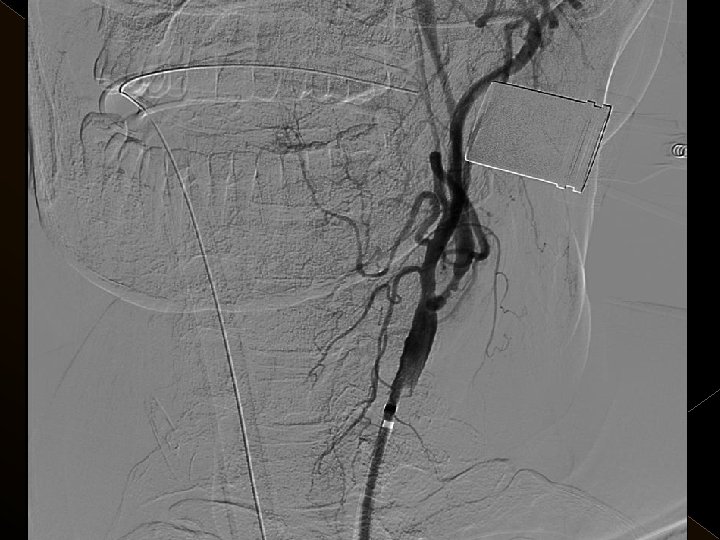

� 25 hasta (16 K, 9 E) , 27 vaskuler okluzyon � 16 orta serebral arter (MCA), � 6 baziler arter ve � 5 internal karotis arter (İCA) düzeyinde olmak üzere � Toplam 25 hasta, 27 tıkanıklığa (6 sı hariç) iv tpa sonrası endovaskuler yolla müdahale edildi

� İnme tedavisinde iv tpa uygulamasını takiben � intraarteriyel (İA) trombolitik tedavi (ia tpa ve ia mekanik trombolizis) � İA stent yardımı ile trombektomi yöntemleri kullanılarak tedaviye cevap ve komplikasyonlar araştırıldı.